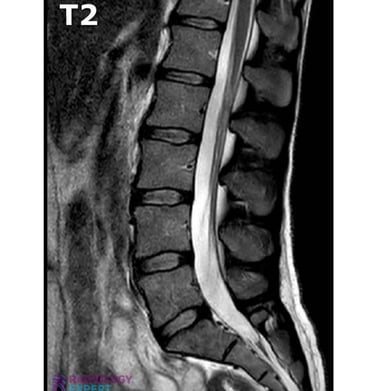

Moments capturing expert trauma and orthopedic care in action